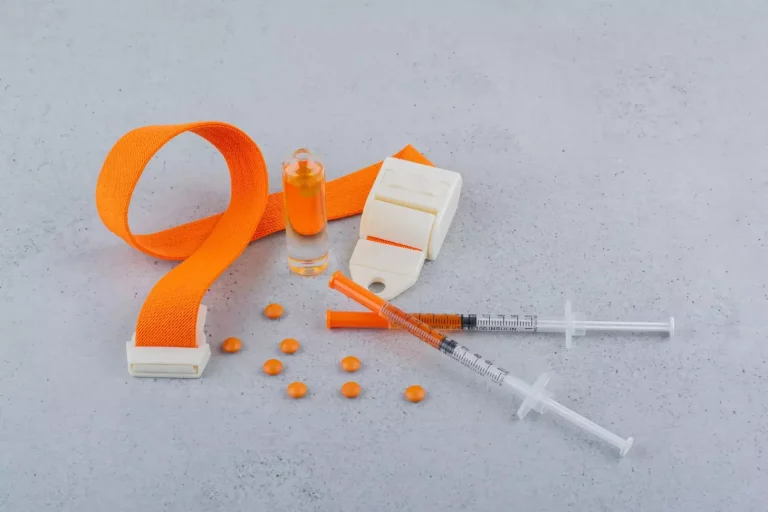

Acute Coronary Syndrome ACLS Protocols

Using ACLS protocols quickly is key for better results in ACS patients. ACLS guidelines help by giving a clear plan for treating ACS. This plan focuses on fast and right actions.

Immediate Interventions in Suspected ACS

When ACS is thought of, quick actions are vital. These include:

- Quick check and sorting

- Starting the cardiac catheterization lab

- First meds like aspirin and nitroglycerin

Quick action can greatly help patients by cutting down time to get a diagnosis and treatment.

Medication Administration Guidelines

Medicine is very important in treating ACS. Guidelines suggest using:

- Aspirin for stopping platelets

- P2Y12 inhibitors to stop more platelet clumping

- Anticoagulants to stop more clots

- Nitrates to ease symptoms and lower heart work

As ACLS guidelines say, “medicines should be chosen and given based on the patient’s specific needs and how they react.”